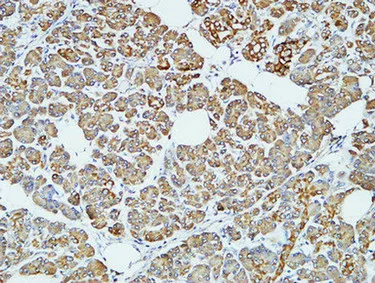

HER2(11H9)Mouse Monoclonal Antibody

Cat: AMM11986

Size1:50μL Price1:$118

Size2:100μL Price2:$220

Size3:200μL Price3:$380

Application:WB,IF-P,IF-F,ICC/IF,IHC-P

Reactivity:Human,Mouse,Rat

Conjugate:Unconjugated

Optional conjugates: Biotin, FITC (free of charge). See other 26 conjugates.

Gene Name:ERBB2